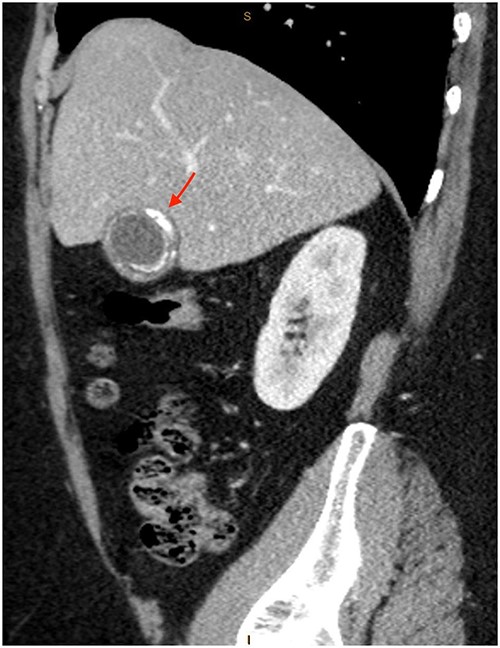

As only part of her gallbladder was imaged on the non-contrast CT lumbar spine, a repeat CT scan of her abdomen and pelvis with portal venous contrast was ordered. This showed semi-annular wall calcification at the gallbladder body suggestive for porcelain gallbladder and several calcified gallstones with largest measuring up to 32 mm (Figs 1–3). No gallbladder soft tissue mass was seen.

Semi-annular wall calcification at the gallbladder body—sagittal view.